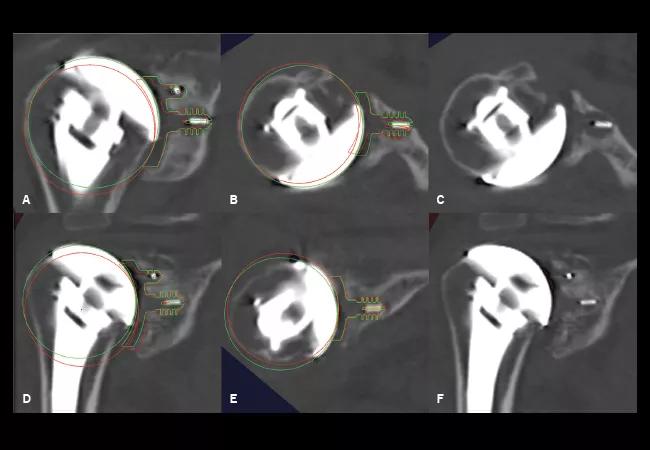

Figure: Digital templates of the position of the glenoid and humeral head components on the immediate postoperative CT (red) and two-year follow-up CT (green) are superimposed on the two-year follow-up CT in two patients (A-C, D-F). In the first patient (A-C), the glenoid component has shifted into increased inclination (A) and retroversion (B), and central anchor peg osteolysis is seen on the two-year follow-up CT after the digital templates are removed (C). In the second patient (D-F), the glenoid component has shifted into increased inclination (D) with stable version (E), and bone integration around the central anchor peg is seen on the two-year follow-up CT after the digital templates are removed (F).

We enrolled 41 patients who had undergone TSA with a polyethylene anchor peg glenoid component for sequential CT scanning and analysis. Each enrollee had a preoperative study (CT1), an early postoperative study within three months of surgery (CT2), and a postoperative study performed at a minimum of two years after surgery (CT3) (see figure). They also had routine plain radiographs and Penn Shoulder Scores at the two-year follow-up visit.

We performed the postoperative CTs using metal artifact reduction techniques. We used a custom 3-D image analysis software to detect the location of the glenoid and humeral head components based on four metal markers embedded in the pegs of the glenoid component and a volumetric center fit to the humeral head component. This technique allowed us to determine glenoid component version, inclination and joint line position. It also allowed us to determine humeral head alignment.